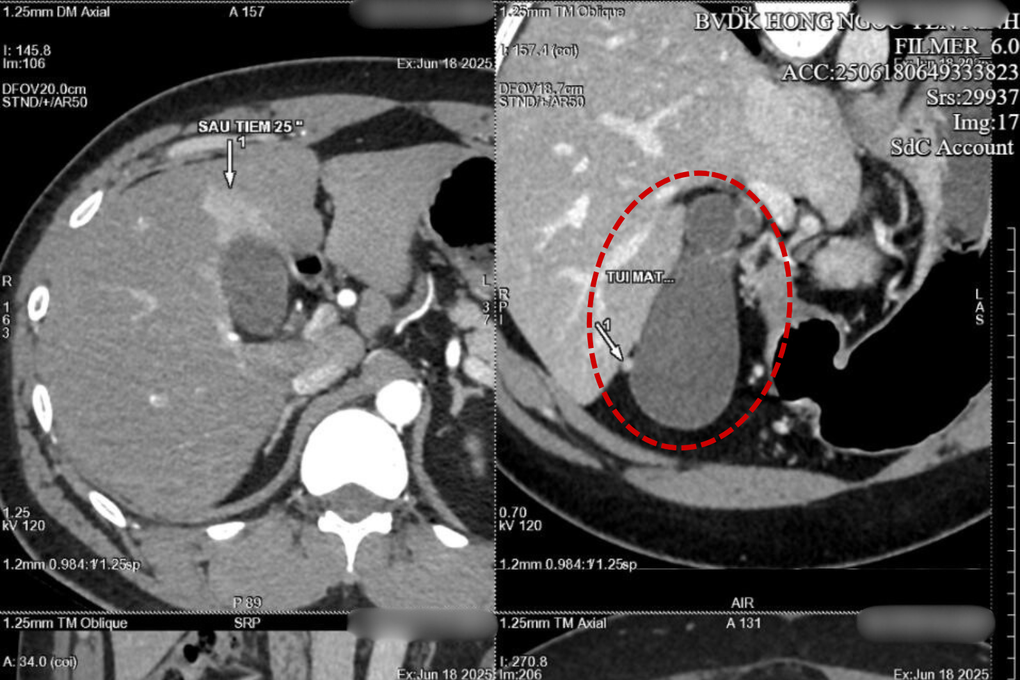

Thăm khám cho thấy bệnh nhân M có túi mật căng to bất thường, đường kính ngang tới 42mm, có hiện tượng thâm nhiễm; bên trong chứa nhiều sỏi, kích thước tới 8.5mm. Bệnh nhân M được chỉ định phẫu thuật cấp cứu ngay sau khi nhập viện.

Túi mật giãn tới 42mm do sỏi (Ảnh: BVCC).